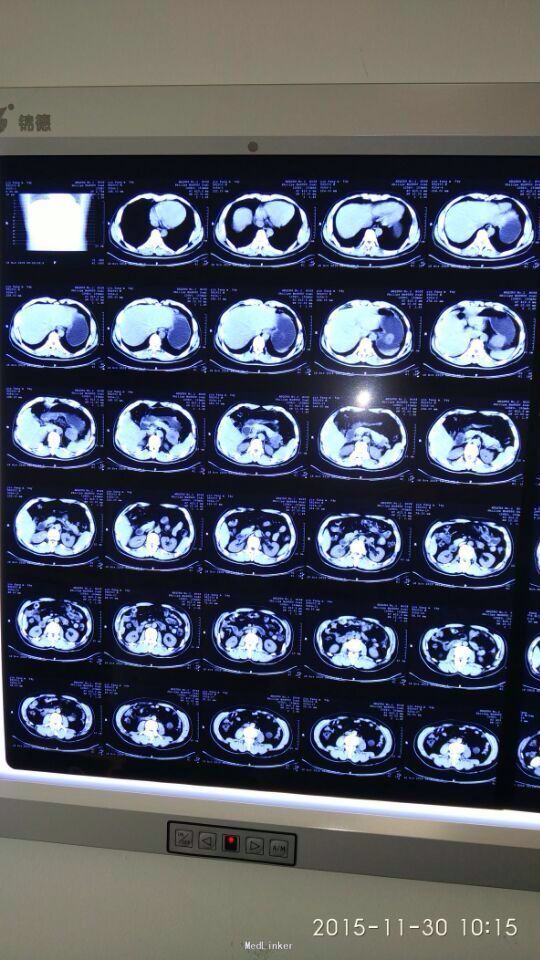

间断性上腹部隐痛,加重两月余。 于15年前左上腹间断隐痛,可忍,伴肩背部放射,活动后缓解,无恶心呕吐,大小便正常,未行特殊处理。2月前,上述症状出现并加重,伴腹泻,伴肩背部放射,无皮肤粘膜黄染。

胃间质瘤 拟行胃间质瘤切除术

瘤体较大,超过5cm,术中注意与胰腺关系,如果压迫胰腺或压迫脾脏血管,是否考虑部分胰腺切除及脾切除,是否考虑胃空肠吻合。